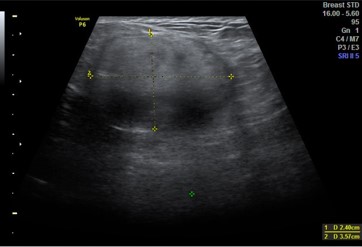

Images 1-3 below show the grossly varied appearances of galactocoele on ultrasound. All three of the following ultrasound images are lesions that were diagnosed as a galactocele after the aspiration.

Image 1